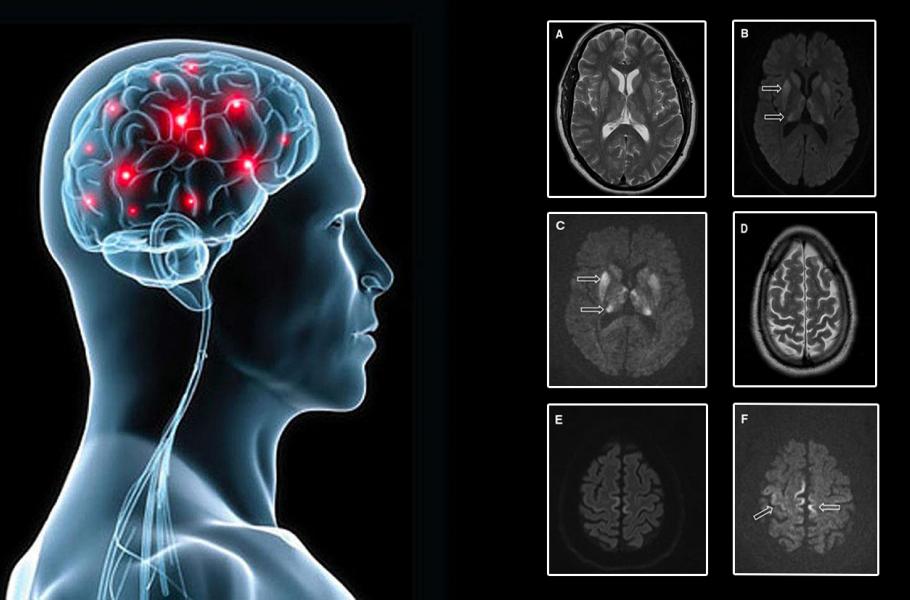

Priony jsou „infekční“ bílkoviny, které se za normálních okolností vyskytují v mozku. Občas se ale stane, že prionová bílkovina změní své uspořádání a složí se do „vadné“ formy. Tato „vadná“ forma je nesmírně odolná vůči všem možným vlivům a hromadí se v mozku. Jde o nevratný proces, který nakonec mozek zničí. Prionová onemocnění jsou naštěstí velice vzácná, ale po určité době stoprocentně končí smrtí.